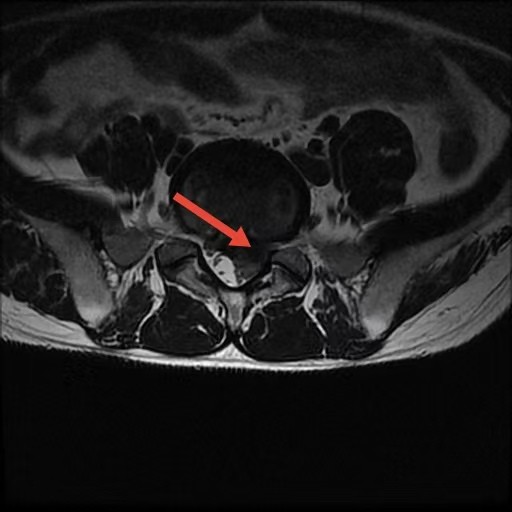

术前

2月7日,我院骨科手术室依旧灯火通明、争分夺秒。手术采用局部麻醉,也摒弃了传统开放手术的长切口,仅在患者腰部打开约1厘米的微小“锁孔”。邱洪九主任团队利用这枚小小的通道,置入脊柱内镜,通过脊柱内镜,清晰定位并精准摘除压迫神经根的“肇事”髓核组织,顺利解除神经压迫、松解受压神经。